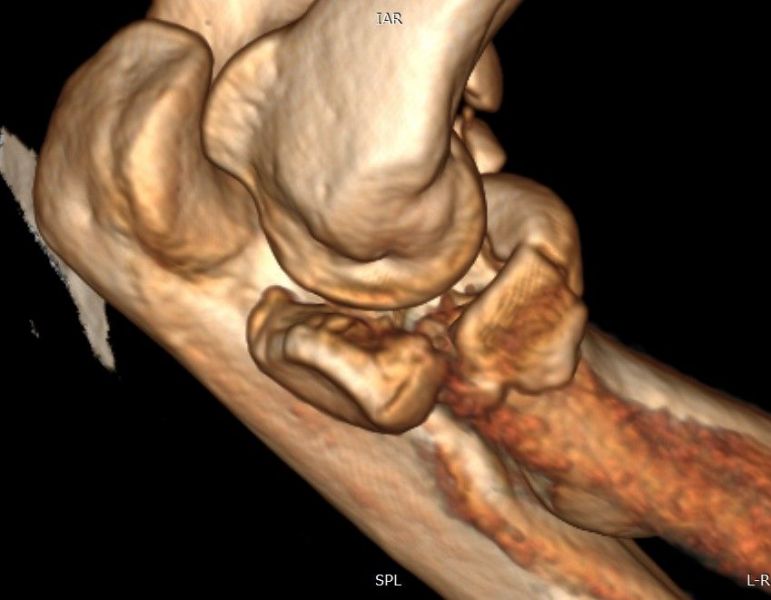

4. Displaced fracture of distal end of the right radius (wrist fracture) in a 63-year-old female.

Treatment. Open reduction internal fixation

I. Before operation, anteroposterior x-ray of the wrist II. Before operation, lateral x-ray of the wrist IIA. Day of procedure, lateral view IIB. Day of procedure, anteroposterior view